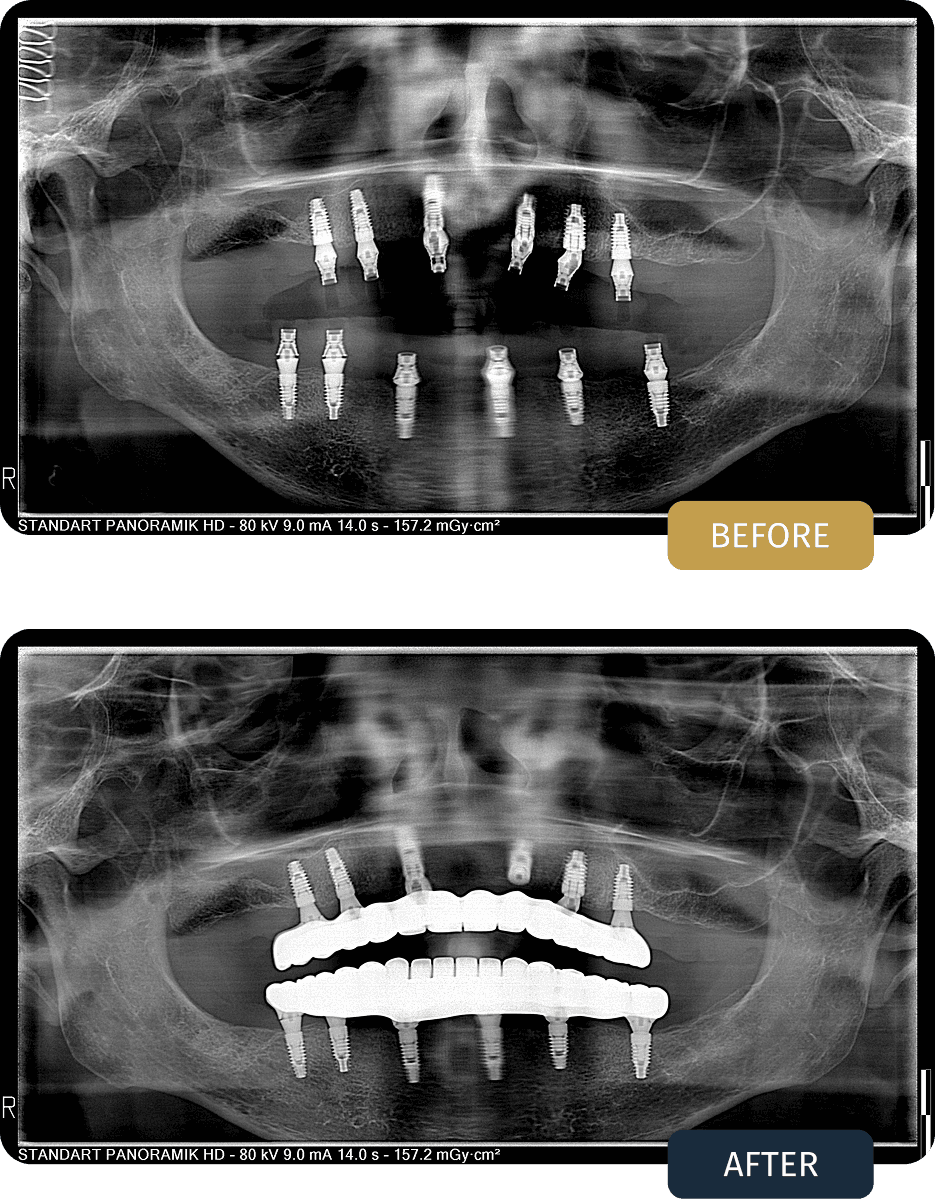

BEFORE

Clinical examination and imaging showed significant tooth loss in both jaws. In the upper jaw, reduced bone height in the posterior regions required additional surgical support to allow safe implant placement. A full arch, implant supported treatment plan was created for both jaws, including closed sinus lifting procedures where needed.

AFTER

Fay underwent full arch rehabilitation with an All on 6 implant treatment in both the upper and lower jaws. Titanium bar frameworks were used to provide maximum strength, long term stability, and even distribution of biting forces.

Two closed sinus lift procedures were performed in the upper jaw to increase bone volume and support secure implant placement without the need for open sinus surgery.